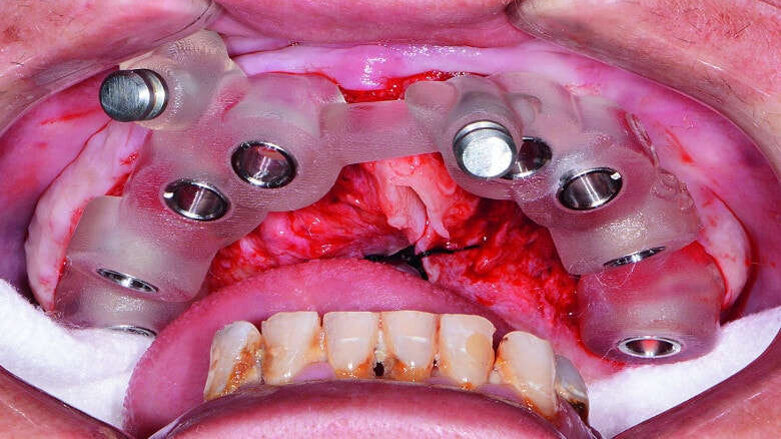

Fig. 9: Placement of maxillary surgical guide.

Fig. 10: Paralleling pins placed.

Fig. 11: Hahn dental implant being inserted.

Fig. 12: Healing caps placed.

At the surgical appointment, intravenous sedation was administered to the patient. The bone-level surgical guide was seated over the patient’s maxilla once the tissue had been reflected, and the fixation pins were tightened (Fig. 9). The implant osteotomies were created following the simplified surgical protocol of the Hahn Tapered Implant System. Eight implants were placed from second molar to second molar in the maxillary arch (Figs. 10 & 11). Healing abutments were connected to the implants to help prepare the soft tissue for the restorative phase (Fig. 12).